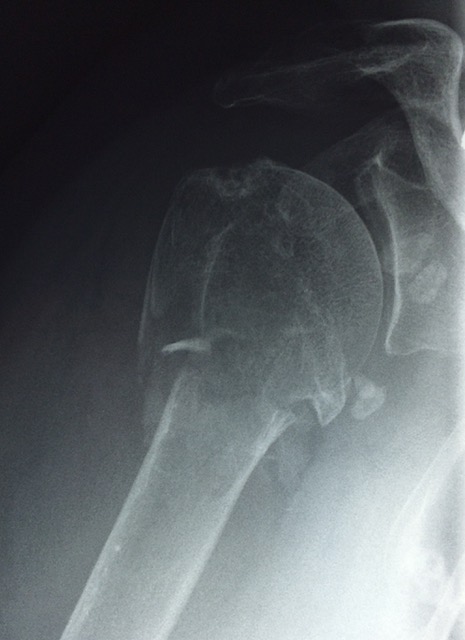

QU’EST-CE QU’UNE FRACTURE DE L’HUMÉRUS PRÈS DE L’ÉPAULE ?

L’épaule est une articulation très mobile composée de plusieurs parties. La partie haute du bras, appelée tête de l’humérus, s’articule avec l’omoplate.

Lors d’une chute sur le bras ou directement sur l’épaule, cette zone peut se casser : c’est ce qu’on appelle une fracture de l’extrémité supérieure de l’humérus.

COMMENT FAIT-ON LE DIAGNOSTIC ?

- Radiographies systématiques

- Scanner si nécessaire pour mieux comprendre le type de fracture et choisir le bon traitement